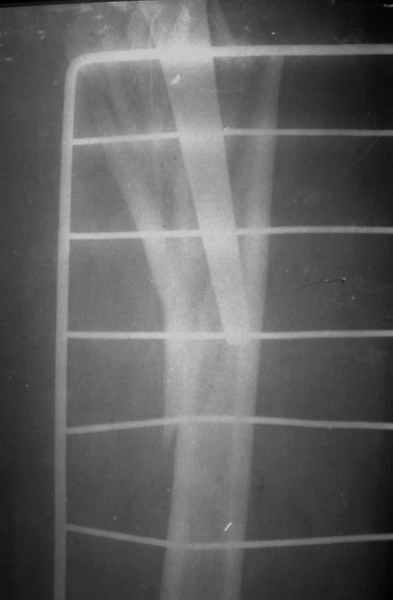

По Ванкуверовской классификации это 2А тип перипротезного перелома на фоне нестабильности ножки эндопротеза и остеолиза проксимального отдела бедра. Решение - удаление предыдущей ножки, имплантация ножки дистальной фиксации. Канал виден на ограниченном участке, исходя из увиденного, я бы предпочел цилиндрическую ножку 200 мм полнопокрытую. Фрагменты собрал бы вокруг ножки серкляжами. Если будут мелкие фрагменты, то есть смысл взять кортикальные аллографты и поджать фрагменты по типу вязанки хвороста. Отношение к чипсам двоякое - на любителя, главное - надежная дистальная фиксация ножки, обеспечивающая первичную стабильность. Что-то похожее мы оперировали несколько лет назад, качество первичных Р-грамм оставляет желать лучшего, но суть понятна. Результаты через 3 года.